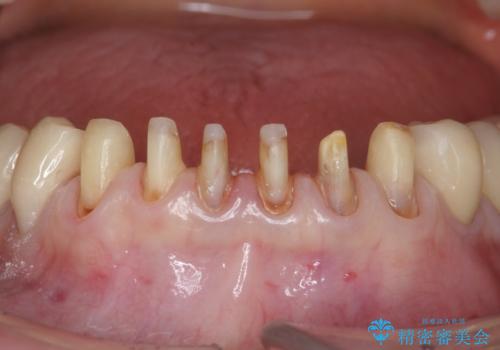

シェーグレン症候群で多発した虫歯 前歯のセラミック治療

- シェーグレン症候群は唾液の分泌が減少し、ドライマウスなど口腔内の乾燥症状が出る疾患です。

唾液分泌が減少すると、虫歯になりやすく、小さな虫歯にコンポジットレジンを充填を繰り返した結果 写真のような継ぎ接ぎだらけの歯になってしまいます。

充填されていたコンポジットレジン・小さな虫歯を丁寧に全て取り除いたのち、歯全体を覆い虫歯の再発予防を期待できるセラミッククラウンで補綴を行います。